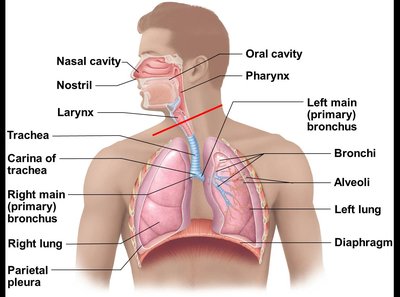

The respiratory system is essential for gas exchange, speech, olfaction, pH regulation, blood pressure control, and aiding venous return. It consists of organs and structures that facilitate the movement of air and the exchange of gases between the atmosphere and the bloodstream.

Major Structures of the Respiratory System

Nasal Cavity and Paranasal Sinuses

The Pharynx

The pharynx is a muscular tube that serves as a passageway for both air and food, divided into three regions:

The Larynx

The Trachea and Bronchial Tree

The trachea is a flexible tube supported by C-shaped cartilage rings, leading to the primary bronchi, which branch into secondary (lobar) and tertiary (segmental) bronchi, and finally into bronchioles and terminal bronchioles.

Lungs and Pleurae

Lung Anatomy

The lungs are divided into lobes and segments, each supplied by its own bronchus and blood vessels. The right lung has three lobes; the left lung has two and a cardiac notch.

Pleurae: Double-layered serous membranes (parietal and visceral) that reduce friction and compartmentalize the lungs.